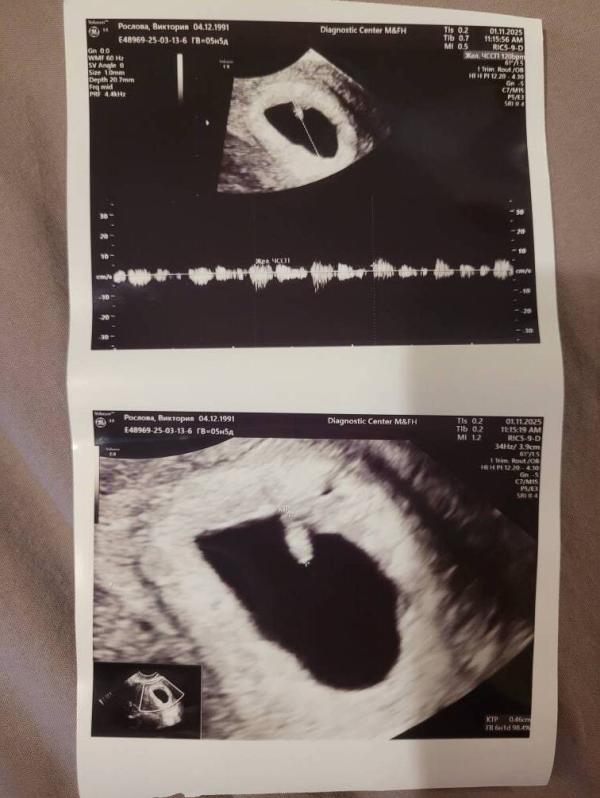

УЗИ показало, что все хорошо, соответствует сроку 6н1д и уже даже бьется маленькое сердечко. 🌟

Когда я услышала стук сердчека (мне включили буквально на секунду) потекли слёзы.

Ни гематом, ни отслоек нет, что лилось - непонятно (после транексам остановилось).